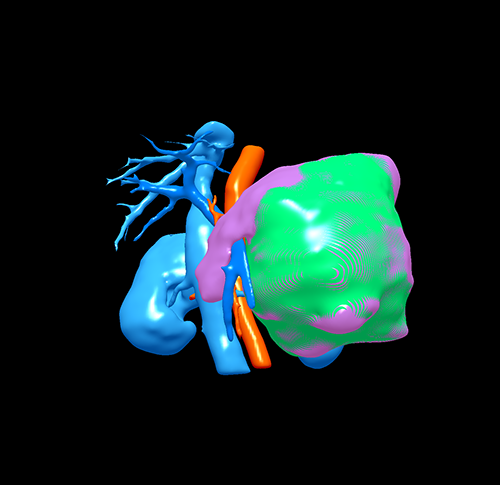

胰体尾囊腺瘤---腹腔镜胰体尾切除